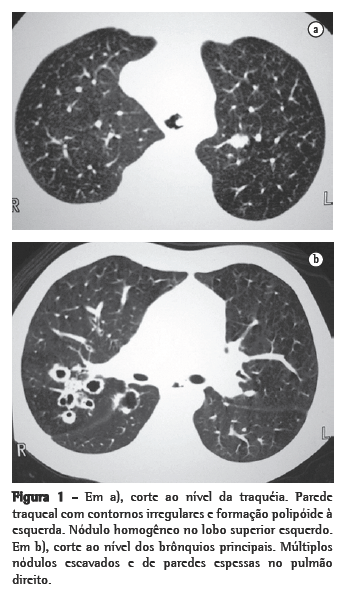

Nos 8 casos foram observadas na TC formações polipóides na traquéia. Em 1 deles, identificou-se também uma lesão em brônquio principal. Sete pacientes mostravam comprometimento do parênquima pulmonar. Em todos foram observadas lesões nodulares escavadas, com contornos internos irregulares, e paredes de espessuras variadas, com aspecto multilobulado em 6 casos, e com confluência das lesões em 5 deles (Figuras 1 a 5). Nódulos sólidos foram vistos em 6 pacientes, Em apenas 1 dos casos foram vistos níveis líquidos. As lesões predominaram nas bases em 3 pacientes, nos terços médios em 2, e em 2 não havia predomínio de distribuição. Em 1 dos pacientes, foi observada associação com massa, e em outro, com consolidação. Neste último paciente (Figura 5) foi constatada degeneração maligna em múltiplas lesões. Sinais de aprisionamento aéreo também foram observados em 1 caso. Em nenhum deles detectou-se linfonodomegalia ou derrame pleural.

A TC, particularmente com aquisição volumétrica (espiral), é superior às radiografias de tórax no reconhecimento de nódulos ainda pequenos, nas fases iniciais de disseminação pulmonar, por sua melhor caracterização e visualização de vegetações nodulares traqueobrônquicas. Os achados tomográficos incluem estreitamento nodular, focal ou difuso, da via aérea. Os nódulos crescem na superfície mucosa, e sua extensão intraluminar é melhor avaliada por TC.(3) São alterações facilmente correlacionadas à doença quando se dispõe da história clínica de papilomatose.(4) Outros achados relacionados à obstrução das vias aéreas e/ou infecções associadas são atelectasias, consolidações, aprisionamento aéreo e bronquiectasias.(2-4) Na nossa casuística, formações polipóides na traquéia foram observadas em todos os exames tomográficos. Sete pacientes mostravam comprometimento do parênquima pulmonar, caracterizado por lesões nodulares escavadas, com contornos internos irregulares, e paredes de espessuras variadas, com aspecto multilobulado e tendendo à confluência. Nódulos sólidos foram vistos em 6 pacientes. Em nenhum deles detectou-se linfonodomegalia ou derrame pleural.